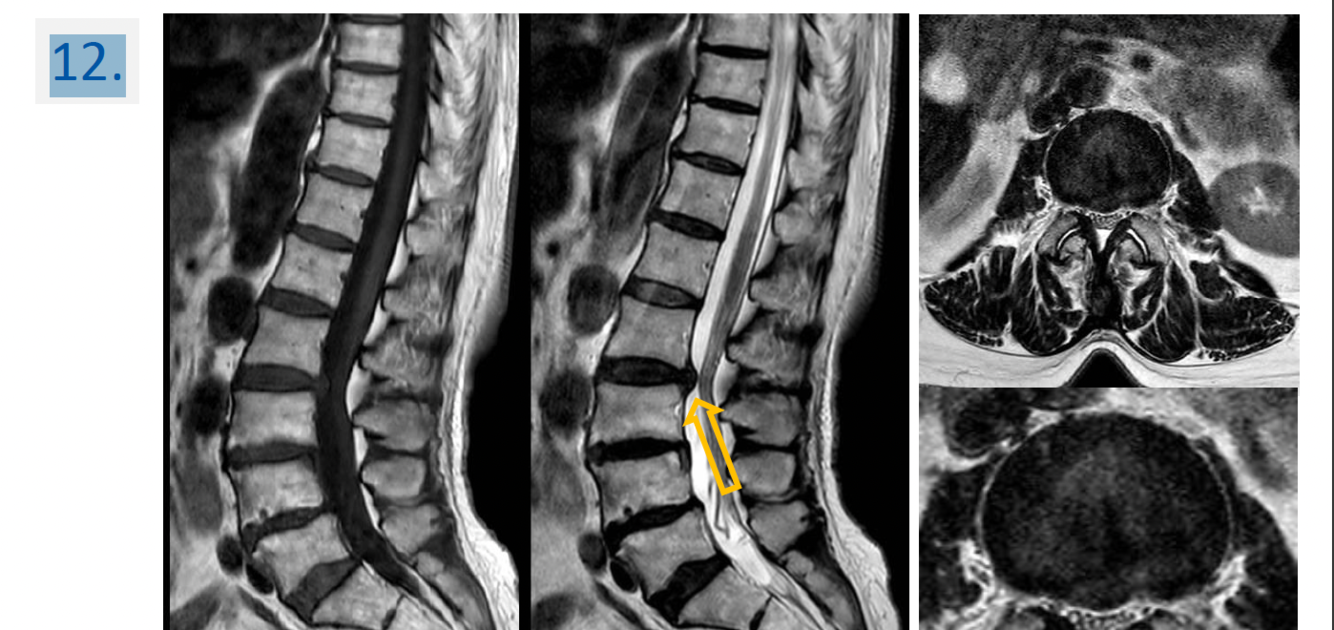

18

Region:

liver right subcostal view

Diagnosis:

Hepatic hemangioma